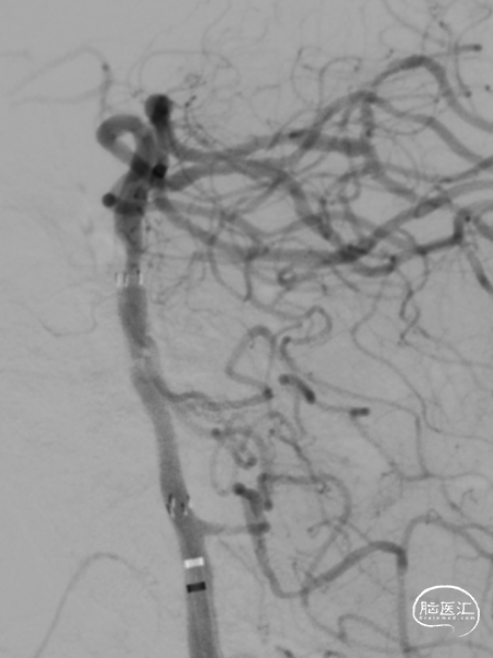

急诊DSA:Ⅱ型弓,基底动脉AICA以远未见显影。

加奇Tethys®中间导引导管到位,明确既往支架位置。但中间导管通过困难。

微导丝微导管通过闭塞段,在右侧大脑后动脉手推造影证实真腔,明确闭塞段,可见造影剂返流至基底动脉尖部,且证明闭塞确为支架内再狭窄导致闭塞。

释放加奇4.0mm*30mm Syphonet®取栓支架,可见支架通体显影。